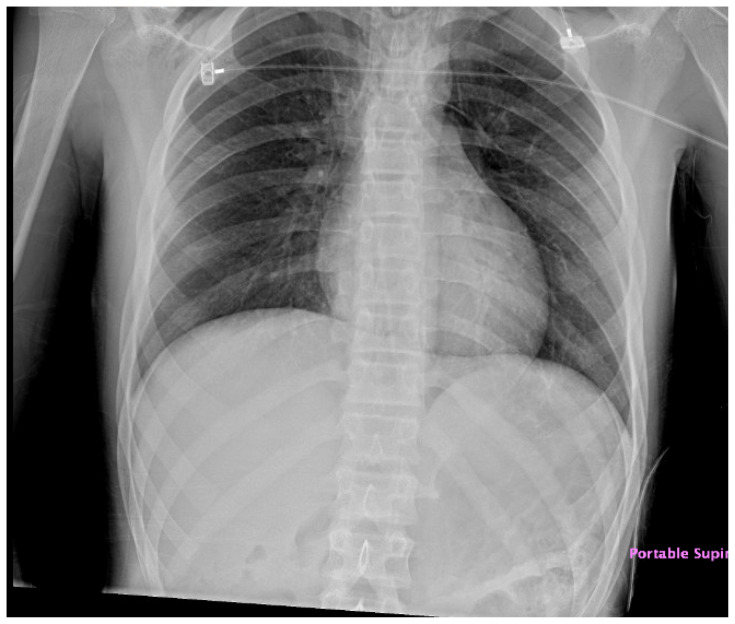

Audience: The target audience of this simulation is emergency medicine residents and medical students. The simulation is based on a real case of a 12-year-old male who presented obtunded with shortness of breath and hypothermia who was ultimately diagnosed with diabetic ketoacidosis (DKA) and pneumomediastinum. This case highlights the diagnosis and management of an adolescent with new onset diabetic ketoacidosis and pneumomediastinum with deterioration of status, as well as important ventilator settings if intubation is required in the setting of diabetic ketoacidosis.

Background: Type 1 diabetes is a common disease in the pediatric population with the prevalence being approximately 2.15 per 1000 youths and diabetic ketoacidosis being the presenting status in 30-40% of the patients.1 Physicians who evaluate a child with altered mental status must have diabetic ketoacidosis in their differential. In the setting of mechanical ventilation in patients with diabetic ketoacidosis (DKA), special care must be taken. Mechanical ventilation in these patients comes with increased risk, morbidity, and mortality. Risk factors for pneumomediastinum include lung disease such as asthma, chronic obstructive pulmonary disease (COPD), and malignancy, but also can occur in the acute setting of vomiting or trauma.2.

Discussion: Diabetic ketoacidosis is a common and critical diagnosis for emergency medicine physicians to consider in the setting of altered mental status in a pediatric patient. This simulation has multiple steps and is based on a real case of an obtunded and hypothermic pediatric patient who was ultimately diagnosed with diabetic ketoacidosis complicated by pneumomediastinum.